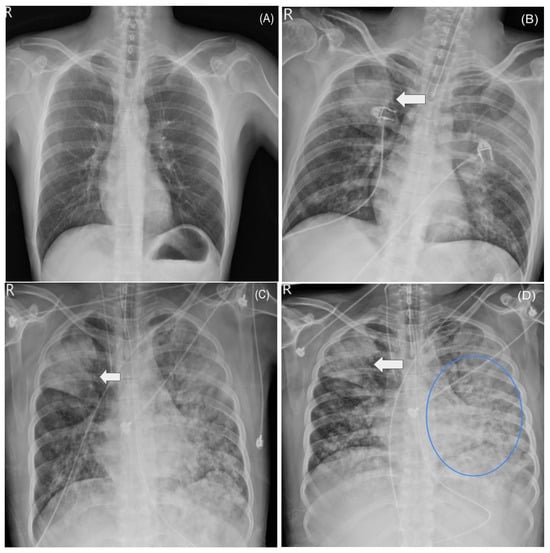

2.3. ICU Course and ARDS

2.5. Supportive Care and Clinical Course

3.1. Clinical Course